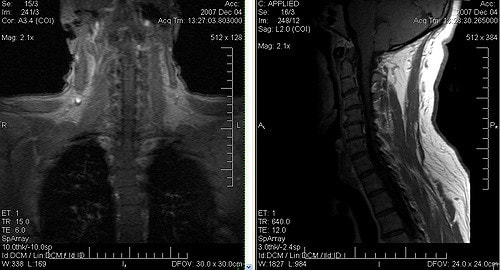

- МРТ шеи и головы.